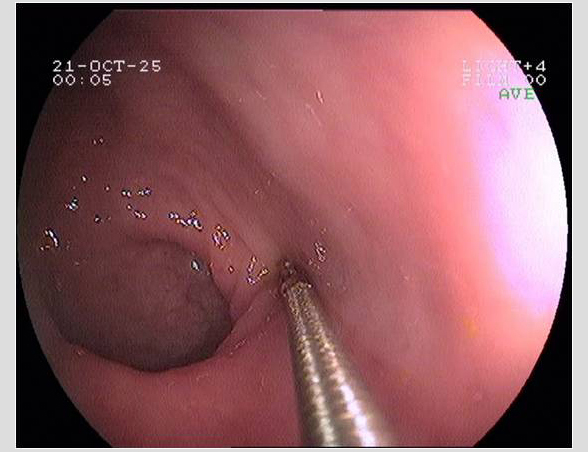

Imágenes tomadas durante la endoscopia digestiva alta y la colonoscopia. Se aprecia una mucosa de aspecto y vascularización normal, sin lesiones visibles. Se progresa con el colonoscopio hasta el íleon. Todo resulta macroscópicamente normal. Se toman biopsias de todos los segmentos explorados.

La endoscopia es el método de elección para el diagnóstico y seguimiento de la EII. Permite una visión macroscópica de la mucosa intestinal y la toma de múltiples biopsias para el estudio histológico.

Realizamos una endoscopia digestiva alta y una colonoscopia a la paciente con toma de biopsias, obteniendo el informe de Anatomía patológica.